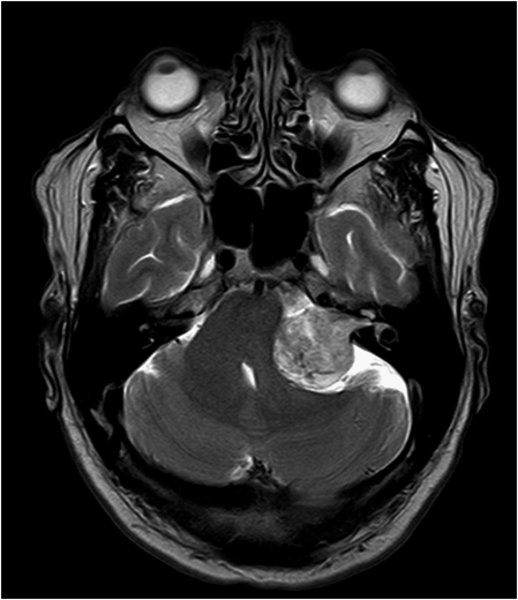

Akustikusneurinom T2 - axial

Akustikusneurinom mit typischem "Eistüten"-Bild.